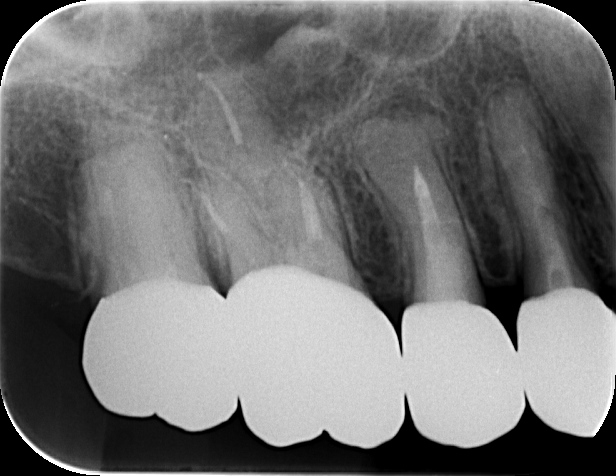

初診時の状態と診断

初診時は痛みがあり、打診痛(叩くと痛い)も認め、咬むことが難しい状態でした。

銀歯(詰め物)が入っていましたが、外して確認すると虫歯が神経まで到達しており、抜髄が必要と判断しました。

そのために、レントゲンだけでなくCTで根管形態を確認し、見落としを減らしたうえで治療方針を立てました。

CTで、右上6番に第2根管(見落とされやすい根管)があることを確認しました。

上顎大臼歯は根管が複雑なことがあり、今回は3根管ではなく4根管としてアプローチ。